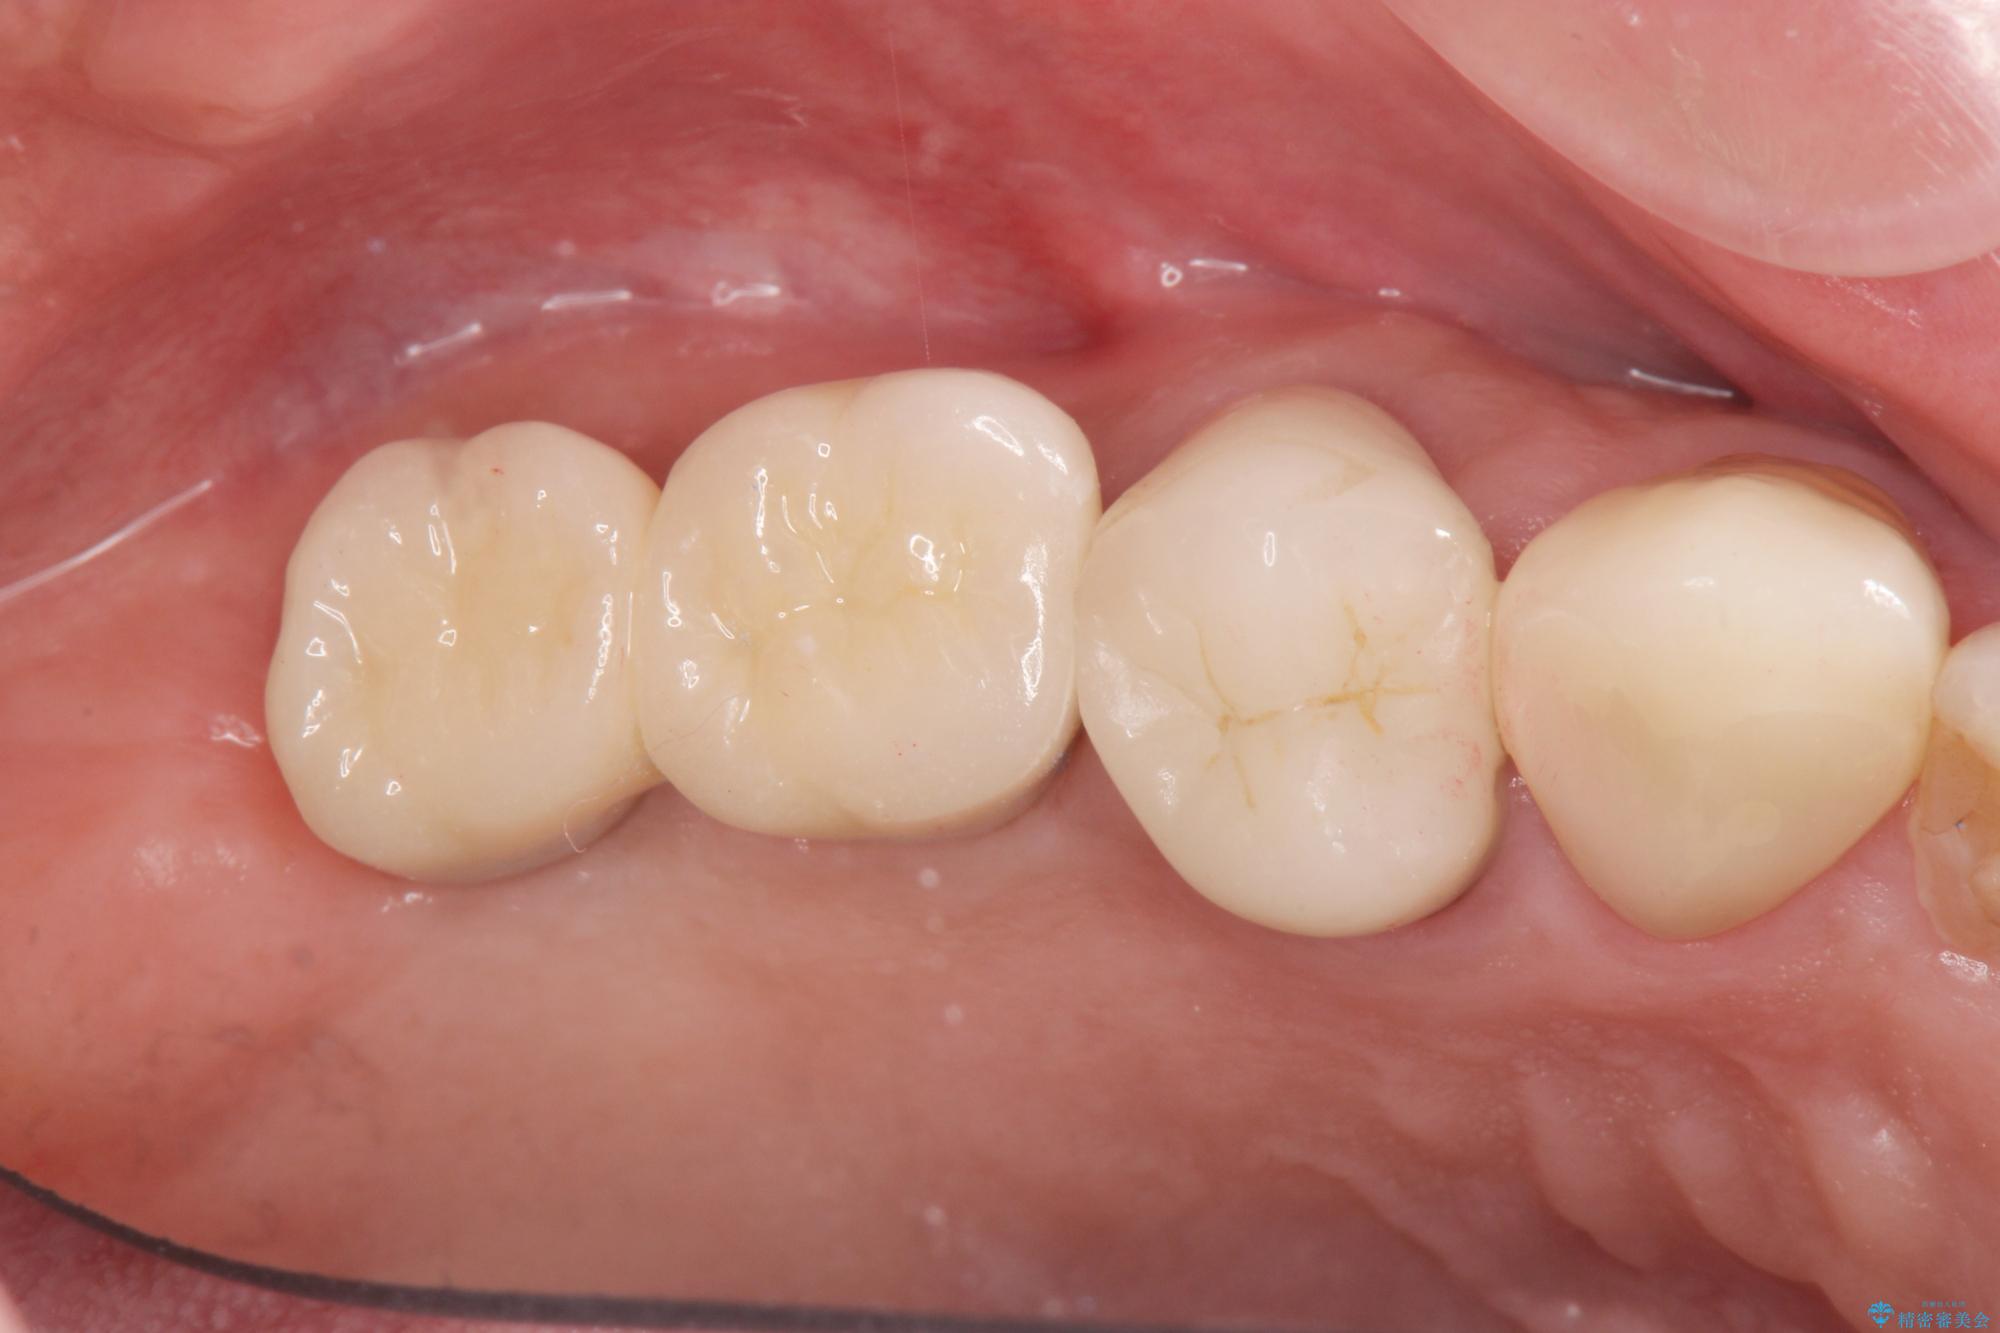

またしっかりと噛めるようになり、食事を楽しめるようになった!と喜んでいただくことができました。

- 88万円(インプラント×2・仮歯×2・チタンカスタムアバットメント×2・ジルコニアクラウン×2)費用は治療当時の料金となります